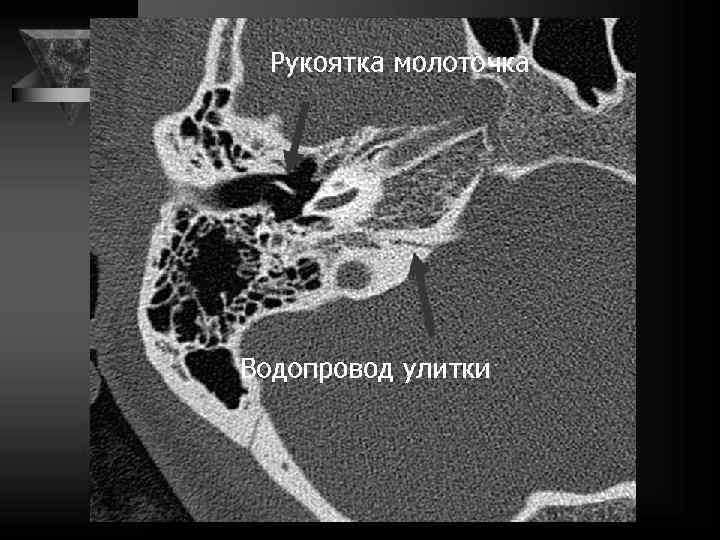

Молоточек 2 головка 3 шейка 4 рукоятка 5 передний отросток 6 латеральный отросток